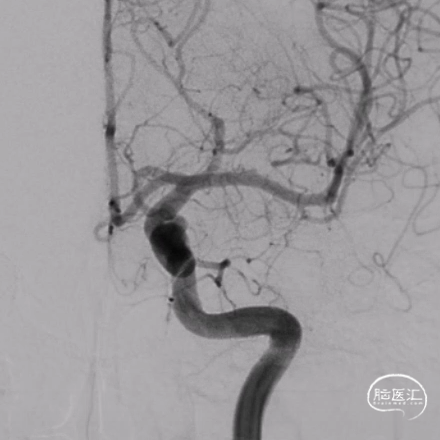

DSA检查提示右侧颈内动脉末端动脉瘤,脉络膜前动脉自瘤颈处发出。

动脉瘤瘤颈约为6.77mm,瘤体大小约为4.19mm*4.85mm。

脉络膜前动脉自瘤颈处发出,且载瘤动脉局部扩张变径,拟行血流导向密网支架置入治疗。